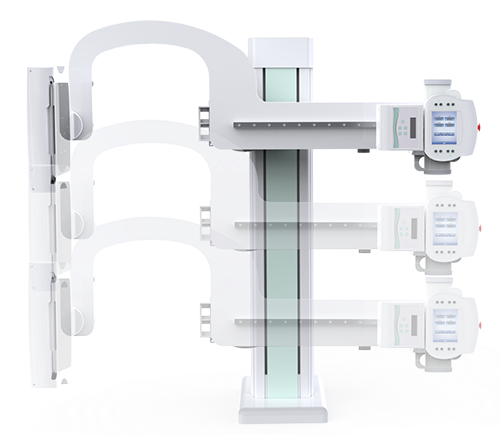

● 可快速選擇、預(yù)設(shè)所需要的視野,節(jié)約擺位時(shí)間;

● 根據(jù)拍攝需求或技師使用習(xí)慣一鍵切換光束范圍;

● 可根據(jù)不同的體位協(xié)議,自動(dòng)調(diào)整光束大小。